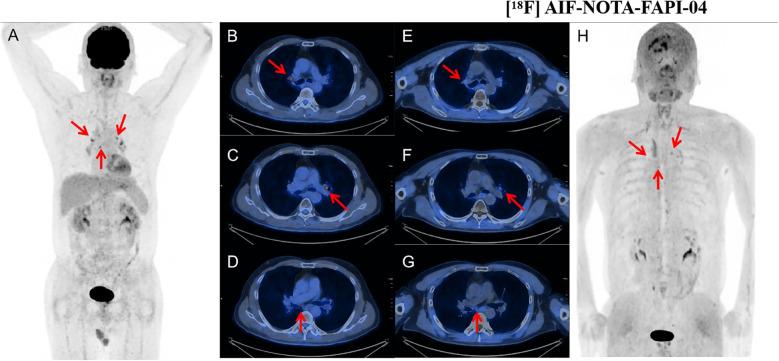

Comparison of [F]AlF-NOTA-FAPI-04 PET/CT and [F]FDG PET/CT for diagnosing lymph node metastasis in malignant tumors.

A total of 41 patients with 126 nodes were included. [F]AlF-NOTA-FAPI-04 outperformed [F]FDG in the detection of metastatic lymph nodes, achieving higher accuracy in both patient-based (92.7% vs. 70.7%, = 0.004) and node-based analyses (91.3% vs. 60.3%, < 0.001). In semi-quantitative analysis, the maximum standardized uptake value and target-to-background ratio of [F]AlF-NOTA-FAPI-04 were higher than those of [F]FDG in metastatic lymph nodes (all < 0.001). Both tracers distinguished metastatic from benign nodes with SAD ≥ 10 mm ( < 0.05). [F]AlF-NOTA-FAPI-04 PET/CT could distinguish between benign and metastatic lymph nodes with SAD < 10 mm ( < 0.001), whereas [F]FDG PET/CT could not ( > 0.05). [F]AlF-NOTA-FAPI-04 also provided more accurate N staging assessments (87.8% vs. 65.9%, = 0.006). [F]AlF-NOTA-FAPI-04 PET/CT enabled the correct diagnosis of more lymph nodes, leading to a change in the therapeutic regimen for eight patients (19.5%).

[F]AlF-NOTA-FAPI-04 PET/CT demonstrated superior diagnostic performance, semi-quantitative capability, and N staging accuracy compared to [F]FDG PET/CT, particularly for small metastatic lymph nodes (SAD < 10 mm), offering enhanced guidance for tumor staging.